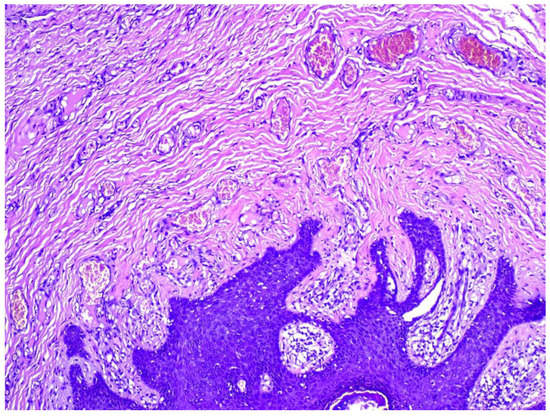

2. Detailed Case Description